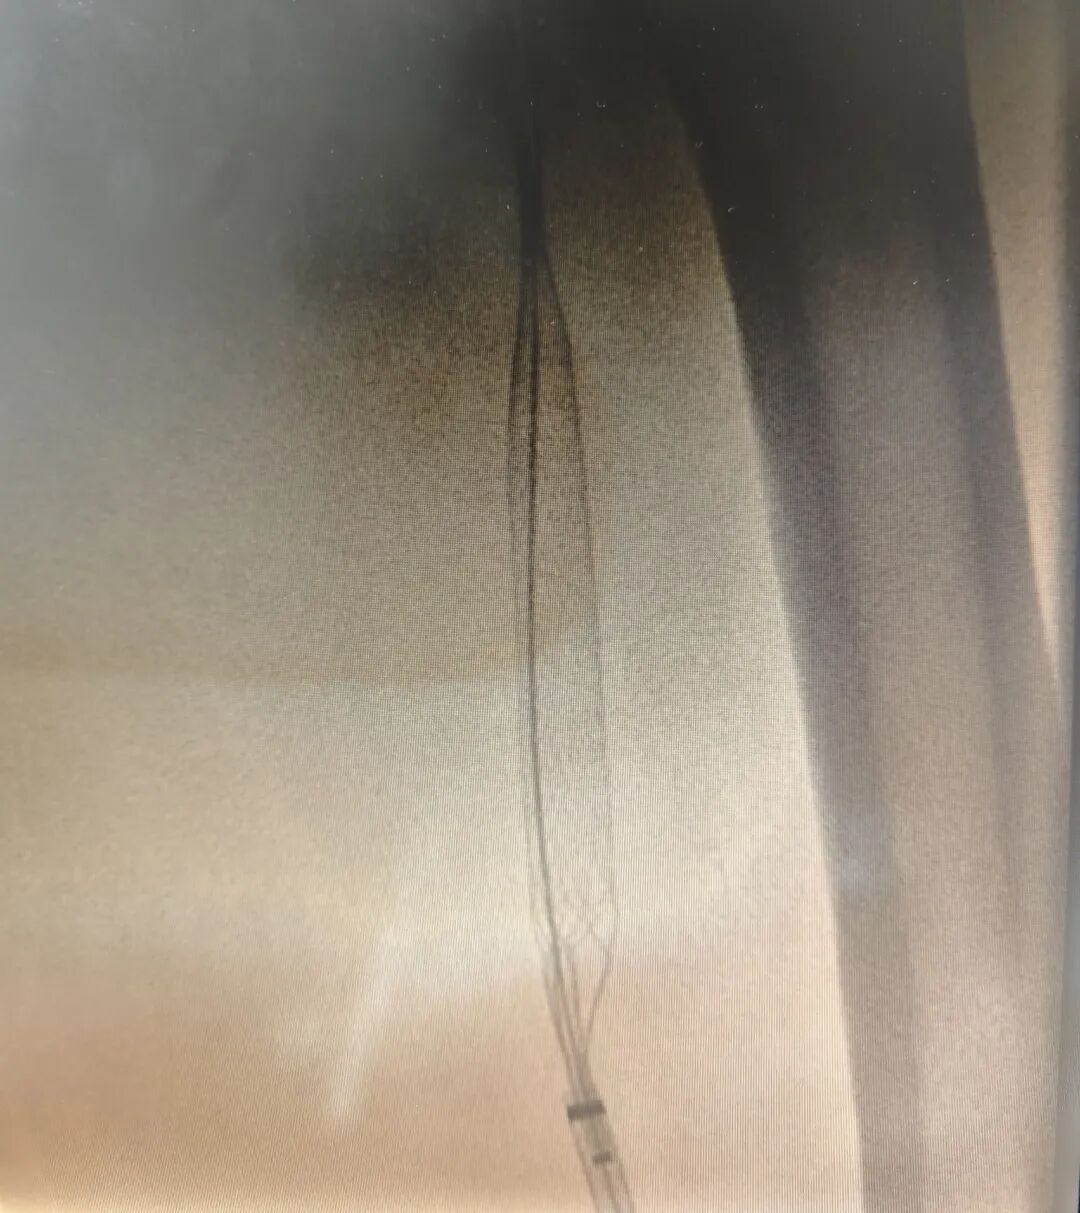

田明主任精准操作,经鞘管将静脉取栓支架推送至髂总静脉,并一路延伸至股浅静脉,通过四次小心翼翼的反复拉栓,成功清除大量血栓。最终,复查造影传来捷报:患者股浅静脉、髂静脉及股静脉血流通畅,未见残余血栓,手术获得圆满成功!这一结果让手术室里的所有人都松了一口气,也意味着这场与病魔的激烈较量取得了阶段性的胜利。

术后造影